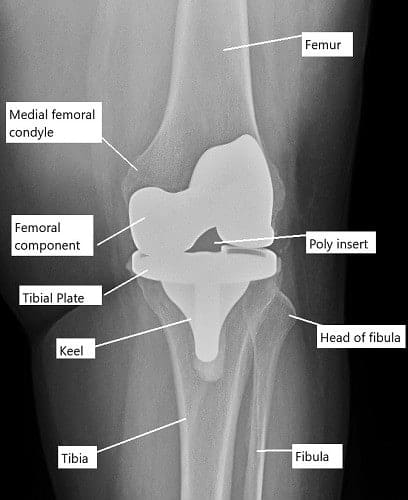

Imagen intraoperatoria que muestra una prótesis total de rodilla.